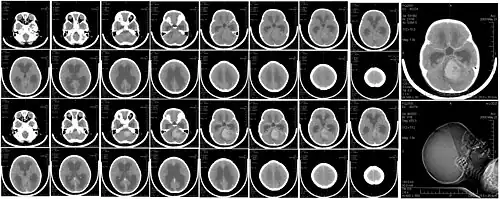

![]() Компьютерная томография головы больного с медуллобластомой | |

Компьютерная томография

В типичных случаях на КТ медуллобластомы определяются как объёмные образования круглой или овальной формы, которые неоднородно накапливают контрастное вещество и располагаются в проекции червя мозжечка. Данные новообразования смещают IV желудочек вентрально. Достаточно часто определяются кисты (до 65 %) и микрокальцинаты[20].